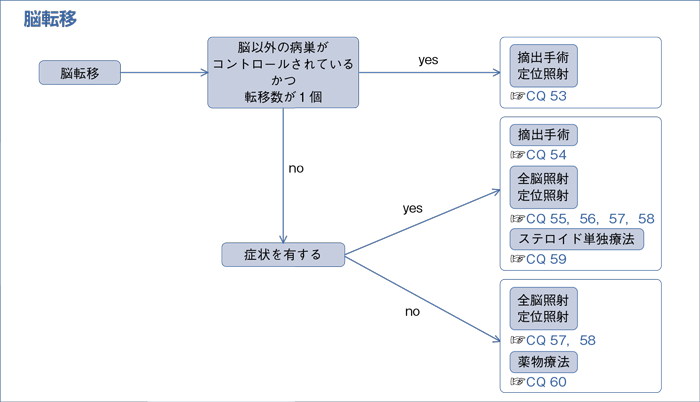

脳腫瘍 成人 治療 国立がん研究センター がん情報サービス 一般の

転移部位別の治療法 再発 転移に対する薬物療法 専門医が解説する